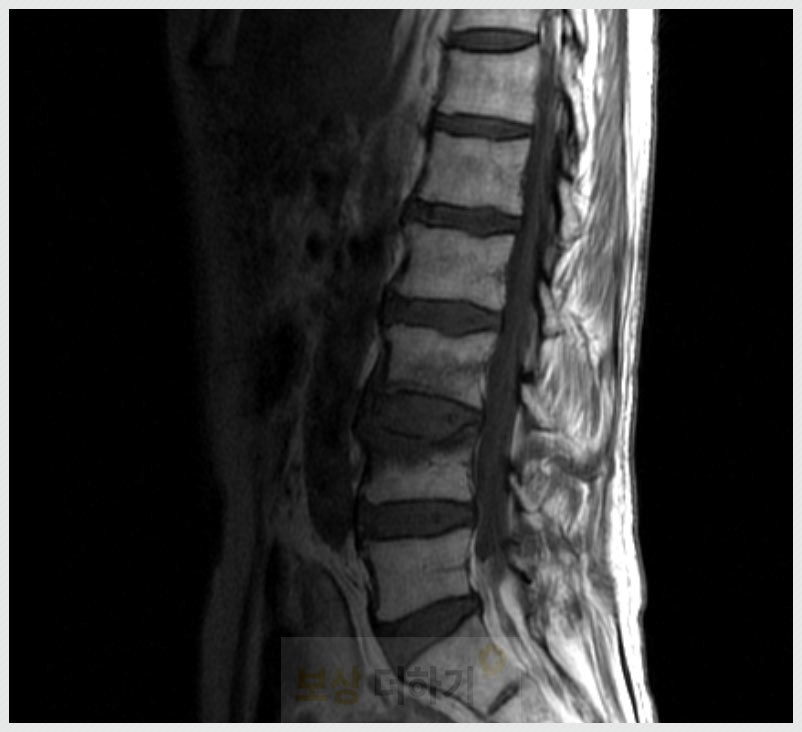

60대 척추 골절 사고 [개.인.보.험] 청구 * 흉추 * 요추

✔ 60대 척추 골절 원인 경추(목), 흉추(등), 요추(허리)

■ 골다공증 나이가 들수록 뼈의 밀도, 강도가 낮아지고 특히 폐경 이후 여성은 골다공증이 급속히 진행됩니다. 골다공증은 뼈 속이 구멍이 많아지고 스펀지처럼 약해지는 질환을 말하는데요. 척추뼈는 원래도 스펀지처럼 다공성이라 이 질환이 있으면 더 쉽게 눌리고 찌그러집니다. ■ 낙상 균형감각이 떨어지고 근력이 약해지면서 미끄러지고 넘어지는 사고가 자주 일어납니다. 만약 뒤로 넘어져 엉덩방아를 찧을 경우 흉추, 요추 등에 골절이 일어나기 쉽습니다.

■ 가벼운 충격 젊은 사람은 견딜 수 있는 충격이라도, 60대 이상의 분들은 허리를 삐끗하거나 재채기, 물건을 드는 동작 등 사소한 자극으로도 발생합니다. ■ 과거 질환 및 생활 습관 척추 수술 이력이 있는 분들 그리고 오랜 좌식 생활, 무리한 허리 사용 등도 누적 손상을 유발합니다.